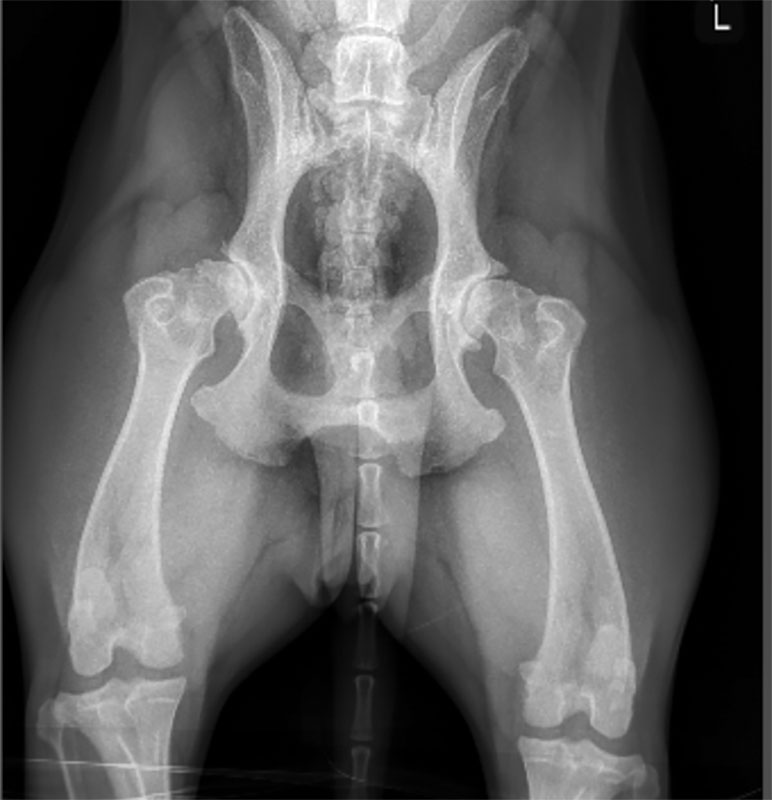

A canine patient with bilateral degenerative joint disease in both coxofemoral joints. Photo courtesy Modern Animal